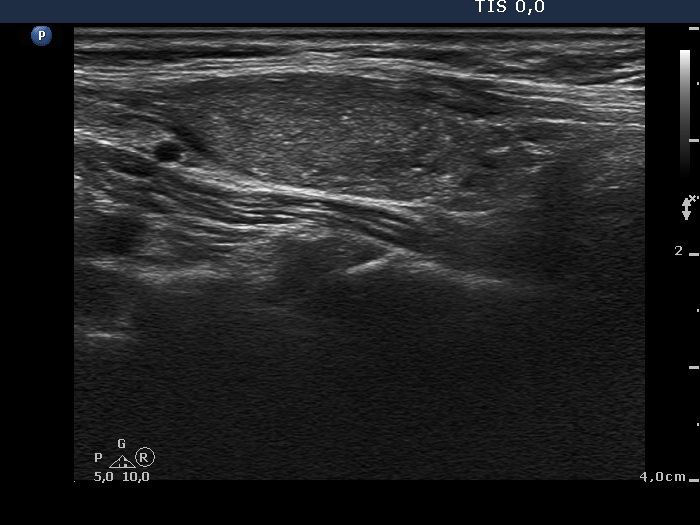

Follicular adenoma (histological diagnosis) - case 1056 |

Papillary carcinoma (histological diagnosis) - case 1074 |

The presentation of the granules is similar in these cases. However the benign lesion has several granules with dorsal tail, therefore these correspond more likely to comet-tail artifacts than to punctate echogenic foci. On the other hand, the complex structures in the malignant nodules are composed of multiple granules. It is worth comparing the figures marked with arrows.